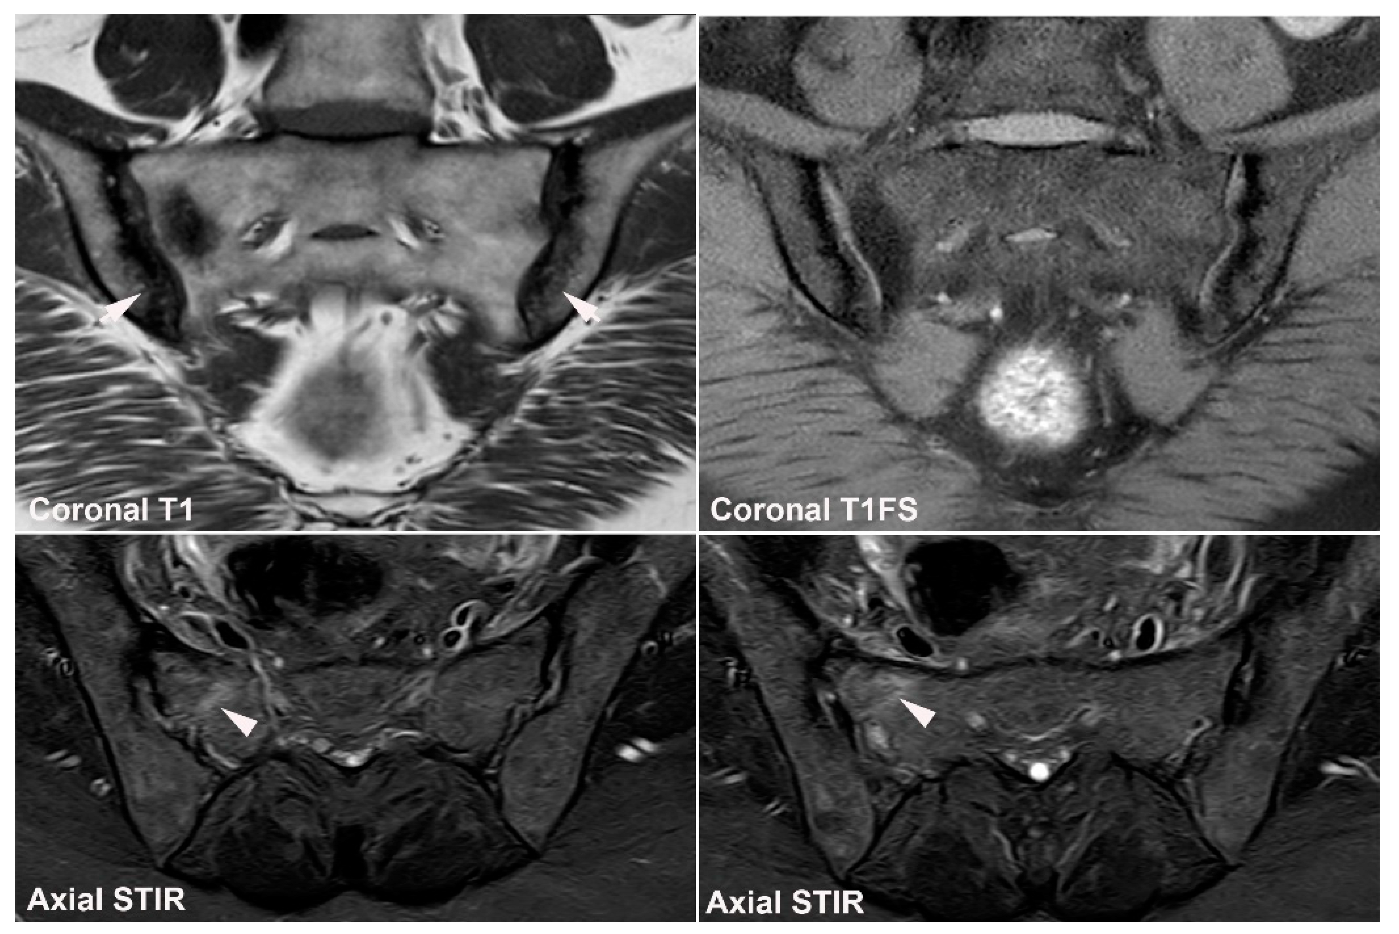

12. Hyperparathyroidism and Other Disorders of Mineral Metabolism

13. Tumors